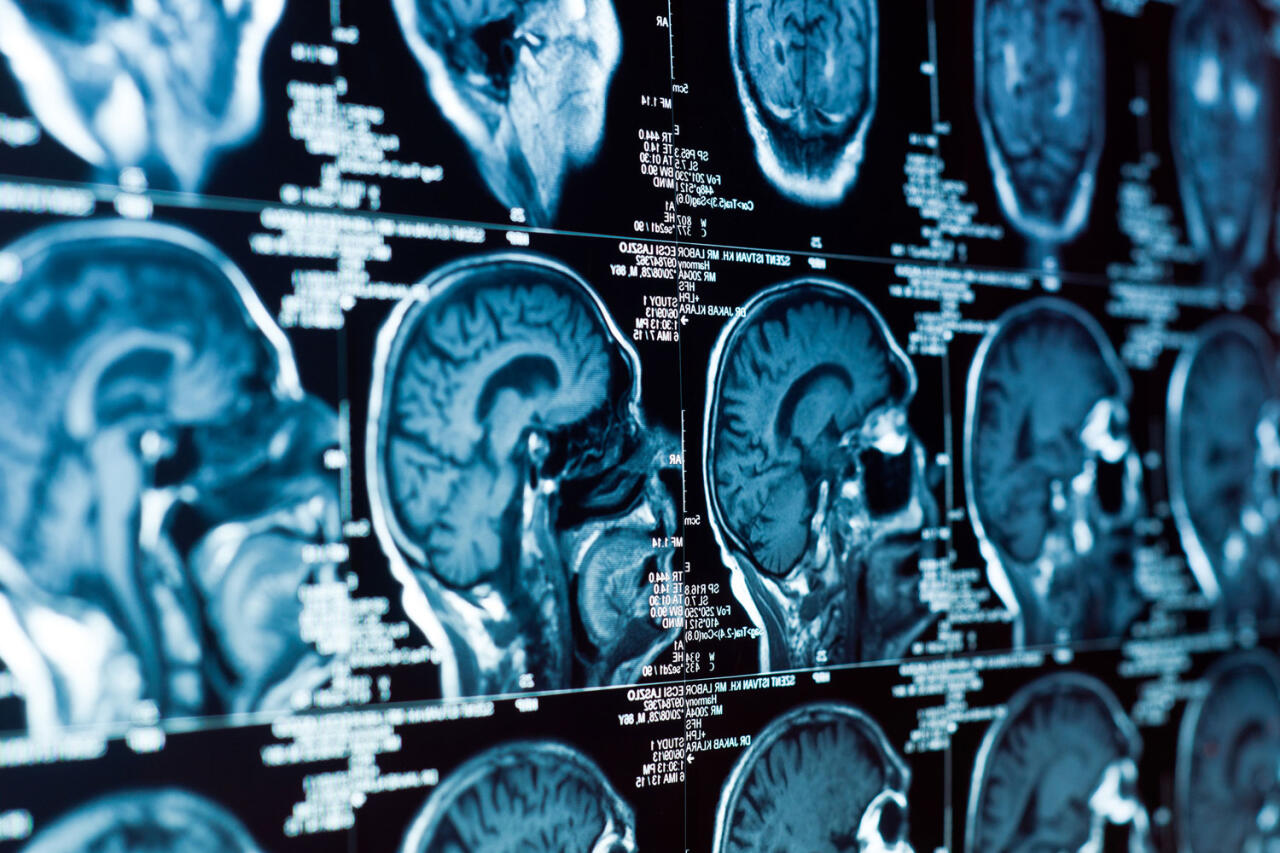

Исследователи из Цюрихского и Нью-Йоркского университетов представили технологию, которая позволяет одновременно и с высокой точностью стимулировать несколько участков мозга с помощью ультразвука. Работа опубликована в журнале Nature Biomedical Engineering (NBE), передает Day.Az со ссылкой на Gazeta.ru.

До сих пор ультразвуковая нейромодуляция позволяла воздействовать лишь на одну точку, причем с ограниченной эффективностью и высоким риском побочных эффектов. Новый прибор, состоящий из сотен миниатюрных излучателей, формирует ультразвуковые импульсы, которые накладываются друг на друга подобно световым волнам в голограмме. Так в мозге возникают несколько фокусных точек, где активируются нейронные сети.

По словам профессора Даниэля Разански, возглавившего проект, воздействие сразу на несколько зон позволяет использовать ультразвук меньшей интенсивности, что делает метод безопаснее. Ранее при слишком слабом воздействии стимуляция оказывалась бесполезной, а при чрезмерно сильном - затрагивала весь мозг и могла повредить ткани.

Технологию испытали на мышах: животным проводили неинвазивную стимуляцию через череп, фиксируя активность нейронных сетей. Ученые предполагают, что эффект ультразвука связан не только с легким локальным нагревом, но и с механическим воздействием на ионные каналы нейронов.

Сейчас метод находится на стадии фундаментальных исследований, но в перспективе может применяться для терапии болезни Альцгеймера, эпилепсии, тремора, болезни Паркинсона и депрессии.